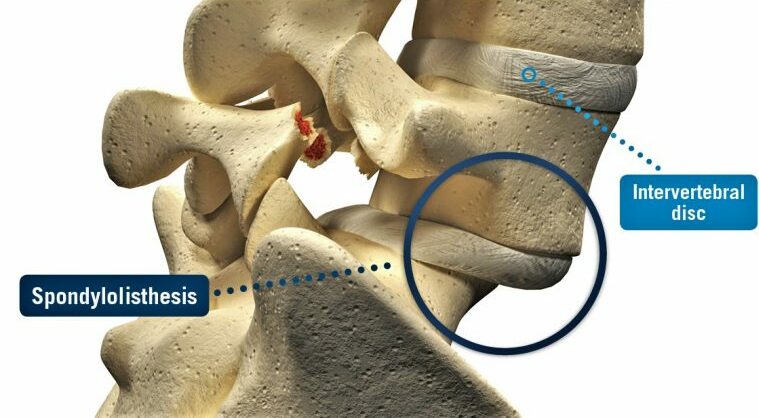

Spondylolisthesis

A condition characterised by the slipping of one vertebra over another

Spondylolisthesis is a condition where one vertebra slips forward over the one beneath it. This can occur in any part of the spine but is most commonly seen in the lower back (lumbar region). The slippage may create spinal instability and, in some cases, place pressure on nearby nerves.

- Palpation of the spine to detect step-offs (where one vertebra feels forward compared to another).